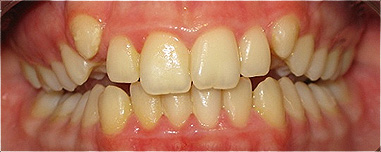

Apinhamento dentário com os dentes caninos em desoclusão (classe II, divisão 2).

![]() |

Após dois anos de tratamento ortodôntico.